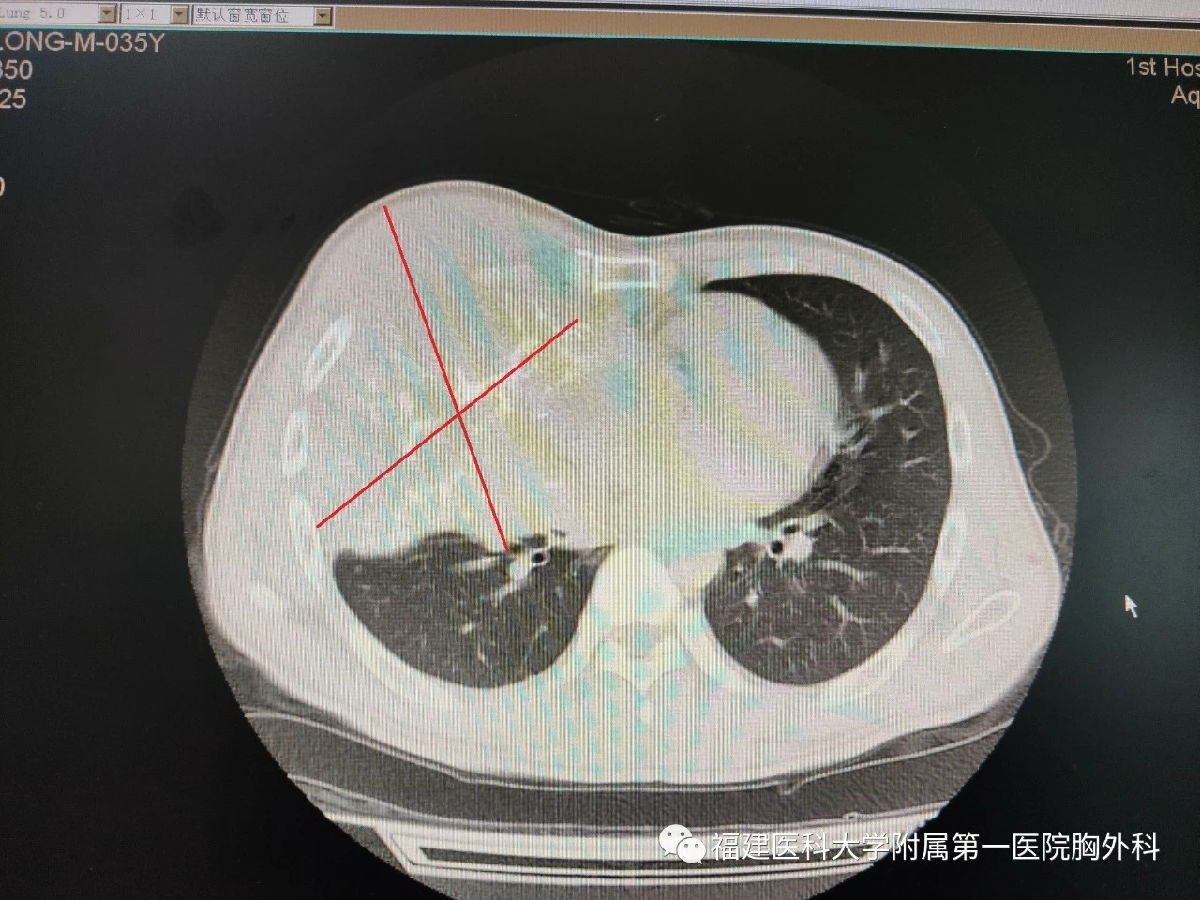

35岁的柯先生三年前发现自己的右侧胸部隐隐作痛,但生活节俭的他觉得忍忍就没事了,没有重视,之后右胸就不断的变大,疼痛也越发剧烈。近半年,每夜疼痛难睡,胸口像压着石头一般喘不过气,也因为胸部隆起明显走在路上更要承受异样的目光,最终,在家人的劝说下前往当地市医院检查。CT报告显示,柯先生右侧胸腔内有巨大肿块,已经侵犯到肋骨,形成巨大囊实性占位,压迫右肺导致右肺肺不张,穿刺病理显示为低度恶性肿瘤,治疗需要将整个巨大肿块完整的切除。但是当地医生表示这样巨大的肿瘤手术难度大,医院设备和技术均没有办法完成这样的手术,柯先生家人带着他辗转邻市多家医院,均是同样的原因无法得到治疗,疼痛和呼吸困难一天天加剧。

“手术风险大,而且肿瘤过于巨大,手术时会比一般的胸壁肿瘤风险更高。如果不做手术,患者右肺肺不张,疼痛难忍,他身体状况将每况愈下,病情只会继续加重。”邱明链副主任医生介绍。

李旭主任表示,手术难度非常大,不确定因素太多了,患者肿瘤体积巨大,血管分布复杂且丰富,瘤体侵犯包绕肋骨,切除过程中肿瘤暴露困难,需要将右侧胸壁四根肋骨和肋间肌一并切除,但这会造成较大的胸壁缺损。为了克服胸壁肿瘤完全切除和胸壁重建这两大难题,李旭、邱明链团队经过反复的讨论沟通,最终确定了手术方案。